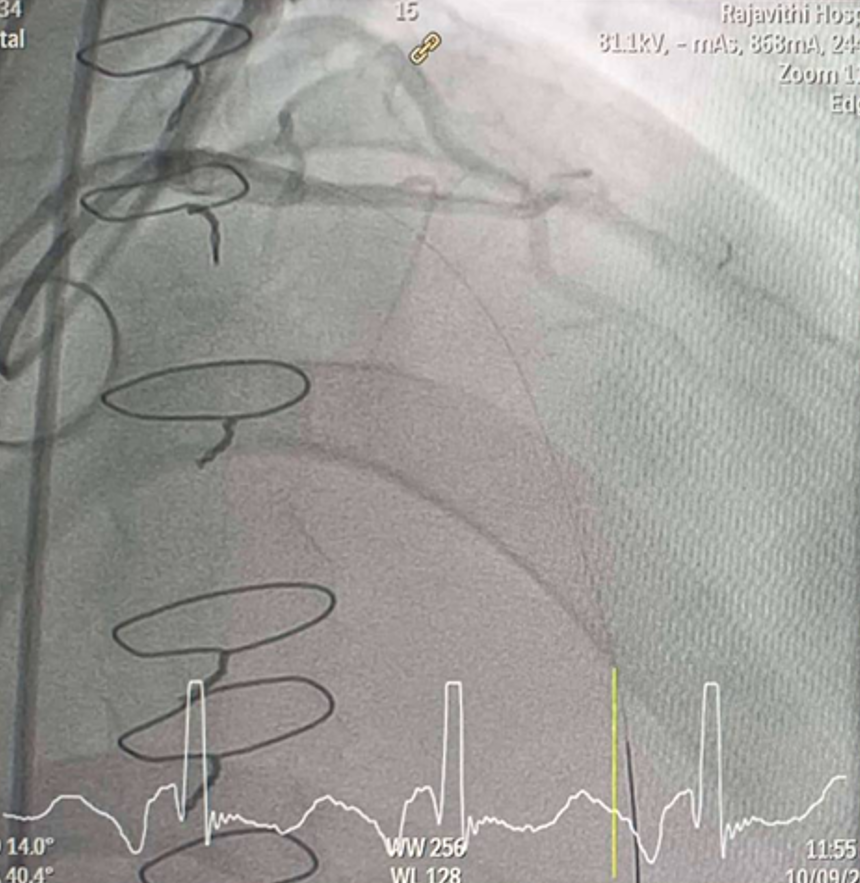

CAG was performed with right femoral approach with JL 4.0/7 Fr, JR 4.0/6 Fr diagnostic catheter showedRight dominantLM : mild irregular, non significant stenosis.LAD : total occlusion mLAD.LCx : mild irregular, non significant stenosis.RCA : non significant stenosis.

Inserted Sion wire and thrombuster to LAD revealed multiple red clots.SC balloon 2.0 x 15 mm, then 2.5 x 15 mm, was inflated at mLAD up to 12 atm. IVUS insertion to LAD revealed vessels’ size LM 5-5.5 mm, pLAD 4-4.5 mm, mLAD 3-3.5 mm with intraluminal thrombus, dLAD 2.75-3 mm. Multiple inflations were done at mLAD with SC balloon 2.5 x 15 mm. After multiple SC balloon inflations, the CAG revealed slow flow phenomenon. Then, the operator performed thrombus aspiration, multiple SC balloon 2.0 x 15 mm inflation and gave IC integrillin 3.4 ml. The final angiogram was acceptable result. The anticoagulant was given after CAG. Chest pain was subsided and hemodynamic parameters remained stable. EKG recorded after angiography showed resolution of ST elevation at V1-3. Later, the patient was discharged with warfarin. The Aortomitral intervalvular fibrosa repair surgery was planned due to embolic complication.